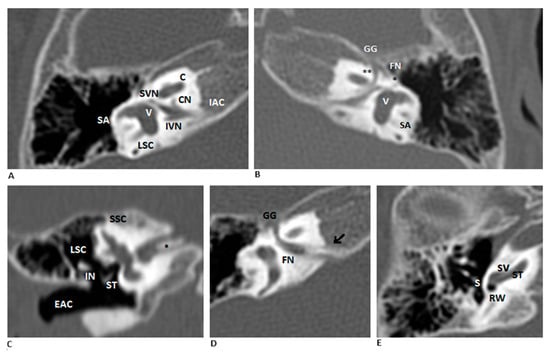

Background: Narrow duplicated internal auditory canal (IAC) is a rare congenital malformation frequently associated with severe-to-profound sensorineural hearing loss. Case Presentation: We present a one-year-old girl with bilateral narrow duplicated IAC and profound hearing loss evaluated through CT/MRI and electrically evoked auditory brainstem [...] Read more.

Background: Narrow duplicated internal auditory canal (IAC) is a rare congenital malformation frequently associated with severe-to-profound sensorineural hearing loss. Case Presentation: We present a one-year-old girl with bilateral narrow duplicated IAC and profound hearing loss evaluated through CT/MRI and electrically evoked auditory brainstem response (EABR). Methods: We conducted a systematic review (1990–2023), identifying 59 published cases of which 24 were bilateral. The mean age at diagnosis was 10.34 years, and 25 cases presented additional inner ear malformations. Only seven patients underwent cochlear implantation, and EABR was performed in four cases. Outcomes of cochlear implantation were heterogeneous. Discussion: In our case, EABR showed a reproducible wave V on the right side, supporting candidacy for cochlear implantation which led to positive early auditory responses. Conclusions: This case and review highlight the role of EABR in identifying residual cochlear nerve functionality and guiding candidacy for cochlear implantation in narrow duplicated IAC. Full article

Figure 1